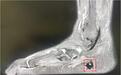

周女士右脚影像图

最近一个月,周女士右脚肿痛加剧,“没有磕着碰着,脚怎么就肿了,现在下地走路都成了件难事。”23日,周女士家人带他来到武汉市第四医院足踝外科中心。经过详细的病史询问、体格检查并结合磁共振检查,接诊的足踝外科一病区负责人黄若昆发现,周女士脚底长了一颗黄豆大小的瘤体。

“结合患者缺磷的症状,有可能是低磷软骨瘤。”黄若昆介绍,低磷软骨瘤临床表现突出,包括进行性骨痛、四肢乏力、活动受限、身高缩短、病理性骨折等。病程早期常被误诊为强直性脊柱炎、原发性骨质疏松等。若能够精确定性、定位后手术彻底切除致病肿瘤,低磷血症可以得到有效纠正,症状可以获得明显改善。

在初步确认了病因后,黄若昆为周女士进行了肿瘤切除手术。术后抽血化验结果显示,周女士血磷指标已从术前正常值的一半恢复到标准值。病理结果也证实肿物为低磷软骨瘤。27日,骨痛症状明显好转的周女士已康复出院。